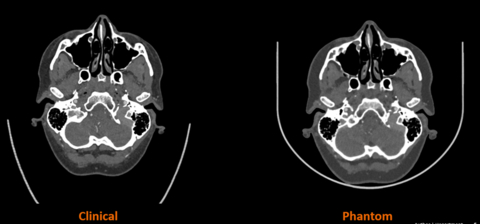

Use of 3D printing may improve outcomes by providing 3D modeling to provider doctors with real scenarios to practice and consult with. (Photo: Business Wire)

A critical tool in medical imaging and an almost universal resource in hospitals worldwide, CT phantoms are specialized devices used to evaluate and ensure the performance of CT scanners. Designed to simulate certain characteristics of the human body, phantoms enable the assessment of various core metrics, including radiation dose and image quality, aiding calibration and safeguarding consistent scanner performance. The joint development leverages Stratasys’ PolyJet™ technology in combination with its unique RadioMatrix™ technology, and Siemens Healthineers’ advanced algorithm aimed at translating scanned patient images into specific material characteristics with radiopacity of human anatomy. The solution will allow for tailored phantom manufacturing and the creation of ultra-realistic human anatomy characteristics with complete radiographic accuracy of patient-specific pathology not previously possible.

Beginning with the manufacturing of 3D printed phantoms for smaller-scale anatomies of the head and neck region, the research will involve the production of progressively larger and complex anatomies – leading up to the Phase One endpoint of 3D printing a heart model and of an entire human torso with complete radiographic accuracy.